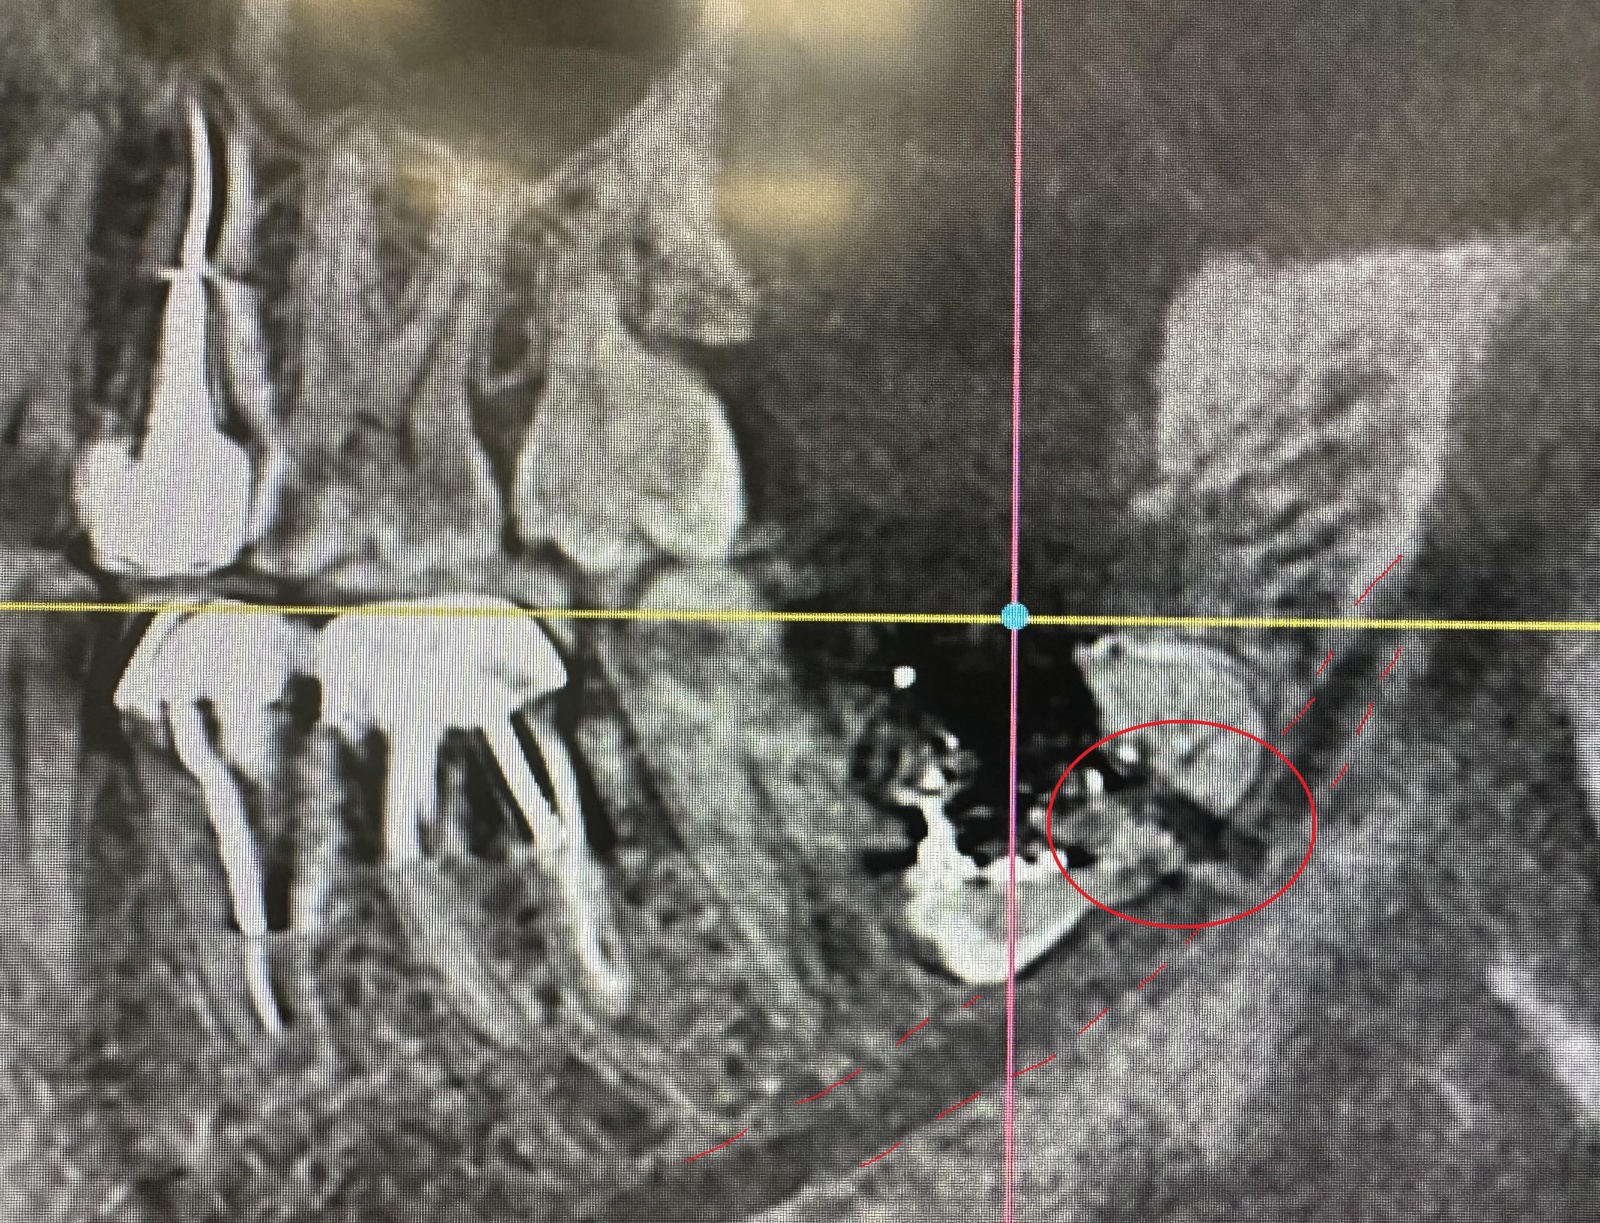

Открываю я снимок и вижу, что действительно так и было:

Черная полоска, уходящая в правый нижний угол картинки, отмеченная кружком, и есть то место, где был перебит нерв.

Белые точки – это остатки йода от йодоформной турунды, которую уложили в больнице (если вы читали выписку). Он рентгеноконтрастен.